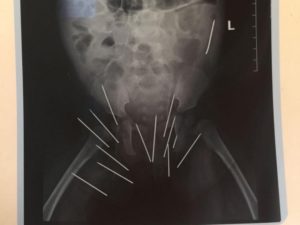

Il mistero della neonata ricoverata in Kenya con 14 aghi conficcati nelle natiche

Una bambina di 10 mesi è stata ricoverata all’ospedale Thika Level Five a Thika, in Kenya, con 14 aghi conficcati nelle natiche.

Per adesso 13 dei 14 aghi da cucito presenti sul corpo della neonata sono stati rimossi chirurgicamente, ma l’ultimo è situato troppo in profondità e la rimozione risulta particolarmente complessa.

I medici temono infatti che la rimozione possa danneggiare i nervi della neonata e altri vasi sanguigni.

“Per quanto sia rischioso rimuovere l’ago, è importante notare che comunque la cosa non mette a rischio la vita della bambina. L’ago è infilato nella profondità della carne, a un livello più profondo degli altri aghi che sono stati rimossi con successo. La bambina dovrà restare in ospedale fintanto che decideremo il da farsi”, spiegano i medici del Thika Level Five.

“La neonata è comunque stabile e in buone condizione”, ha detto Jacob Toro, direttore dei servizi medici nella contea di Kiambu  in Kenya.

La bambina di nome Baby Jane Wairimu è stata ricoverata in ospedale a novembre dopo che sua madre, Jacinta Ndung’e, si è accorta del dolore che provava la neonata ogni volta che la si provava a mettere seduta.

“Quando ho portato mia figlia in ospedale non sapevamo cosa avesse”, racconta la madre. “Durante un cambio di pannolini in ospedale mi sono accorta che qualcosa di appuntito mi aveva punto le dita, così ho chiamato l’infermiera che tramite una leggera incisione si è accorta del primo ago conficcato nel corpo di mia figlia”, ha proseguito Jacinta Ndung’e.

La donna però non è stata in grado di fornire una spiegazione su come gli aghi siano entrati nel corpo della figlia.

“Non credo né nella stregoneria né porto rancore verso nessuno. Questa è un’esperienza sconcertante”, ha concluso.